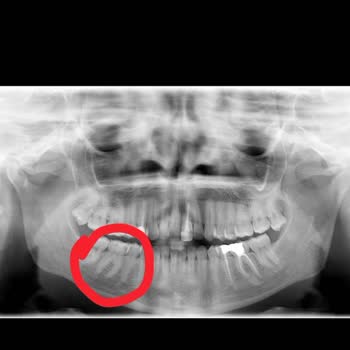

Adana Seyhan’daki Fatma Kemal Timuçin Diş Hastanesi’nde, doktor **** tarafından yapılan implant tedavim sırasında ve sonrasında hem sağlık açısından hem de davranış açısından çok olumsuz bir süreç yaşadım. İmplantlarımdan rahatsız olduğumu, sorun yaşadığımı doktora ilettiğimde, kendisi bana hakaret ...